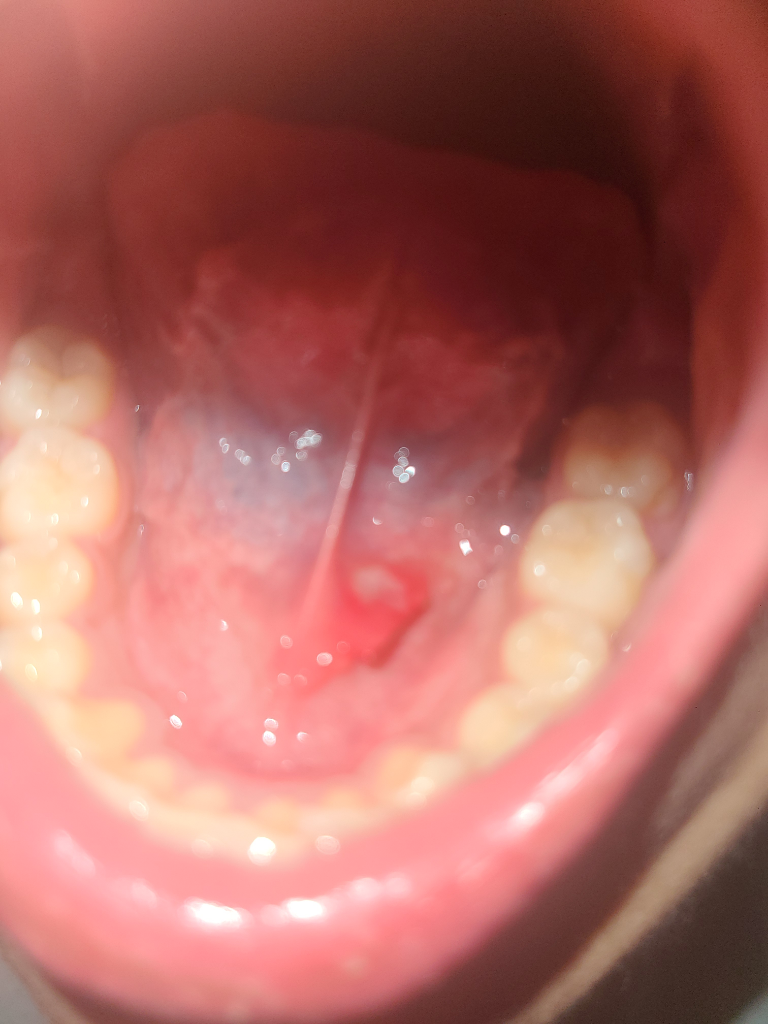

혀 밑에 고름같은게 있는데 이게 뭘까요?

혀 밑에 피맛같은게나고 안에 이물감이있어 입을 열어보니 사진과같은 고름? 염증?같은게 나 있는데 이건 어떻게 치료를 해야할까요?

해당부위는 구내염이 생긴것으로 보입니다.

구내염은 몸의 면역력이 떨어졌을때 구강점막에 손상이 되어 생기게 됩니다.

혀밑에 하얗게 보이는 것은 구내염으로 보입니다. 통상 혓바늘이라고도 합니다. 그냥두면 1-2주 지나면 저절로 없어집니다.